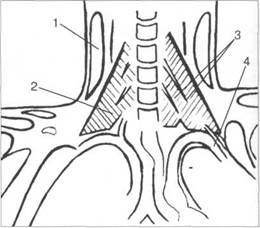

[W.Swobodnic, M. Herrmann].

a. carotis dextra; a. carotis sinistra; cartilago thy-roidea; a. thyroidea superior; v. thyroidea superior; v. jugularis interna; a. subclavia dextra; v. subclavia dextra; a. subclavia sinistra; v. thyroidea inferior; v. thyroidea superior im-par; trancusbrachiocephalicus; v. brachiocephalica dextra; v. brachiocephalica sinister; a. subclavia; a. pulmonalis;